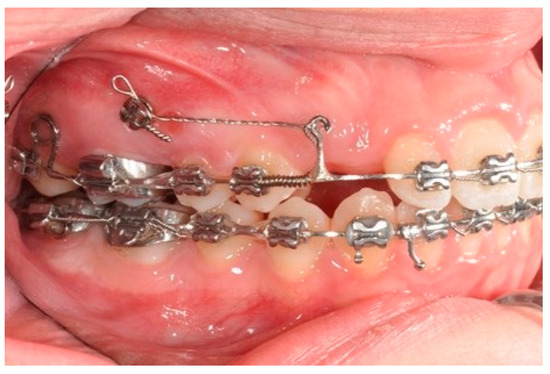

After achieving the full bonding on the upper arch, two miniscrews (tads) are placed between the upper first molars and the second bicuspid, bilaterally. A 0.19 × 0.25 SS wire is shaped, adding a helical bulbous loop, bent lingually, flush to the second molar tube. At the same time, an active 7° lingual crown torque is placed on the second molar. A long spur with a mesial hook, just mesial to the bracket of the second bicuspid, is soldered. A metallic ligature is placed between the tads and the spurs.

The helical bulbous loop produces space distally to the upper first molars. An open coil is added between the second bicuspid and the first molar in order to move to the distal second and first molar at the same time (Figure 4 and Figure 5). Eventually, an elastic module is placed between the hooks on the second molars and the first molars in order to finish the combined distalization of the upper first molars.

Figure 4. Molar and premolar distalization strategy.

Figure 6. Molar and premolar distalization strategy: Hooks are placed between the laterals and the cuspids. Third-class elastics (1/4” 6 0z) are placed from the tads to the hooks.